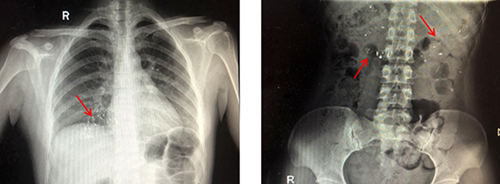

医生解释,水银体温计是由玻璃和金属汞构成,咬碎后的碎片可能会导致口腔、咽喉部、胃肠道黏膜的损伤,严重者甚至会导致穿孔。水银经胃肠道吸收甚微,但误吞水银者如果胃肠道黏膜有溃疡伤口,水银便会经溃疡或者伤口立刻进入人体血液,这样吸收的汞会产生较大的毒性,严重可危及生命安全。而及时摄入蛋清、牛奶等可有效保护消化道黏膜,减少毒物的吸收。后经急诊科医护人员进行专业的清理口腔,洗胃,催吐,加速排泄等措施,终于将孩子肠胃内残留的水银排泄干净。

首先,让孩子立即离开打碎水银的房间,仔细观察孩子口腔是否有划伤,取出孩子口中的玻璃碎片。接下来,看孩子的手指是否被划伤,清理孩子接触汞的部位。对于吞服了水银的宝宝,可以先让他喝一些蛋清、牛奶或豆浆保护胃肠黏膜;最后,尽快带孩子去医院就诊。处理完孩子这边,就是对于环境的处理了。暴露在空气中的水银很容易挥发到空气,但这比误吞入肚的水银更危险。因为水银在空气中挥发后,会变成汞蒸气,它很容易被吸入体内,从而引起中毒。由于水银在高温下更容易挥发,所以要立即关闭暖气。关闭所有通向其他房间的门窗,打开被污染的房间的门窗,保持至少24小时的通风。用小铲子或戴上手套用湿润的小棉棒或胶带纸将洒落在地面上的水银粘集起来并放入密封小瓶中;然后在瓶中加入少量水,并在瓶上写明“废弃水银”等辨识性文字后,丢至合适的垃圾桶里。

医生补充提醒,除了水银温度计,学龄前期的孩子对外界充满好奇心,但是没有安全意识,硬币、纽扣、发夹、电池、小磁铁、枣核、小钉子等都是危险品,这些异物容易损伤消化道、气管,甚至引起窒息等危及生命,因此,家长应时刻看护好孩子,避开或避免接触危险异物。一旦出现误吞或误吸异物,请及时就医。